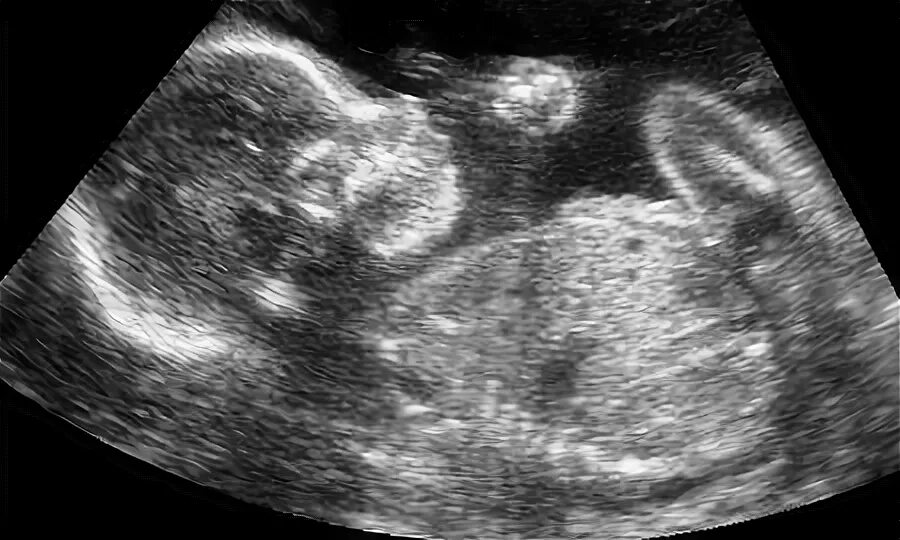

Как выглядит ребенок 38 недели